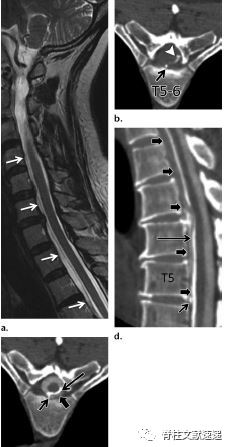

图注:钙化椎间盘及骨赘导致脊液漏

图注:一位47岁女性因钙化椎间盘后方骨赘导致硬脑膜撕裂、脑脊液漏和颅内压过低。

钙化椎间盘及骨赘导致脊液漏

1998年,Vishteh等人首次描述了腹侧硬膜外间隙钙化椎间盘骨赘导致脊髓脑脊液漏的原因。

钙化的椎间盘组织或骨赘骨刺导致硬脑膜缺损、由此产生的脑脊液漏和脑脊液低颅压表现。C5–T7常见。

图注:5岁女孩出现症状性儿童钙化性椎间盘炎,颈部疼痛3周,无外伤史。出现斜颈,活动受限。随访6个月后 CT图像显示突出部分的钙化点被吸收,C3/4髓核仅有微小的残余钙化(箭头)。3个月后疼痛几乎完全缓解,6个月随访时疼痛完全缓解。

患者症状主要发生在颈椎,颈部或背部疼痛、斜颈和活动受限最常见。

急性疼痛,自发缓解较快;神经系统症状不常见;治疗的主要方法是保守治疗。